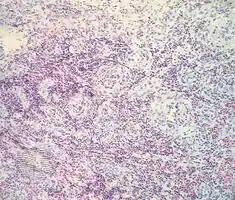

- Angiolymphoid hyperplasia with eosinophilia/pathology